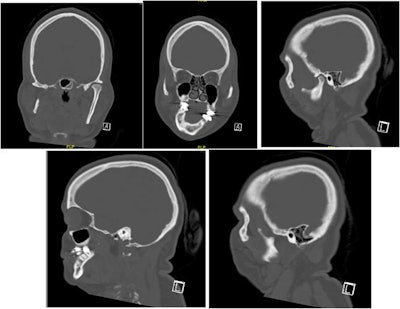

Selected computed tomography (CT) scan slices show mandibular and maxillary hypoplasia and condylar resorption on the right side.

Selected computed tomography (CT) scan slices show mandibular and maxillary hypoplasia and condylar resorption on the right side.In December 2020, she was placed under general anesthesia and underwent the following procedures: